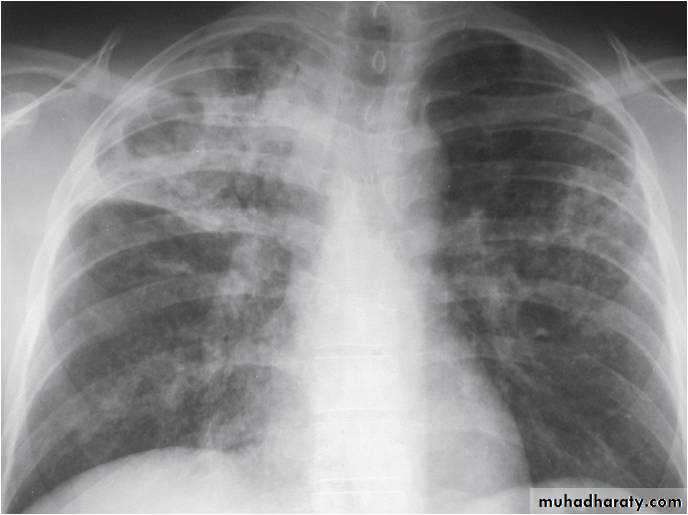

Post primary TB broncho pneumoniacotton wool sign

Post primary TB Bronch pneumonia

60.post primary TB ( cotton wool appearance )

61.post primary TB notice upper apical Broncho pneumonic shadow